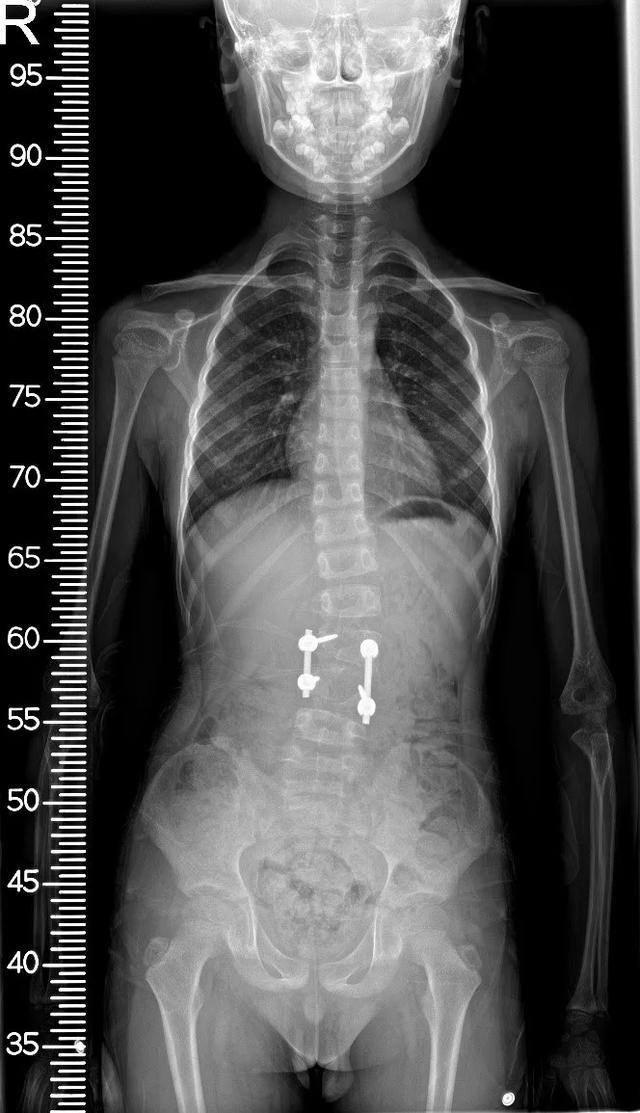

术后正位

术后侧位